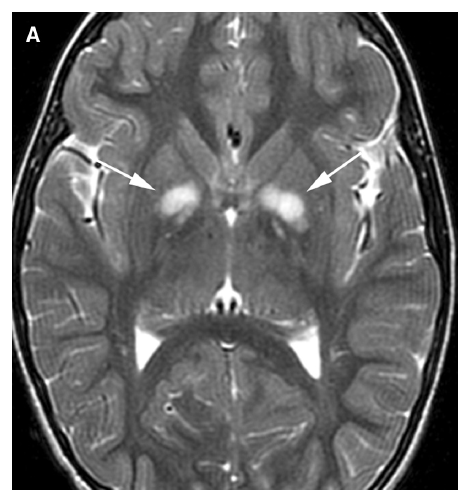

What are the imaging characteristics of NF spots of myelin vacuolization?

Increased white matter volume of corpus callosum

Increased ADC signal T2 hyperintensity in brainstem, cerebellum, thalamus, internal capsule, CC but spares subcortical white matter and centrum semiovale

T1 isointense